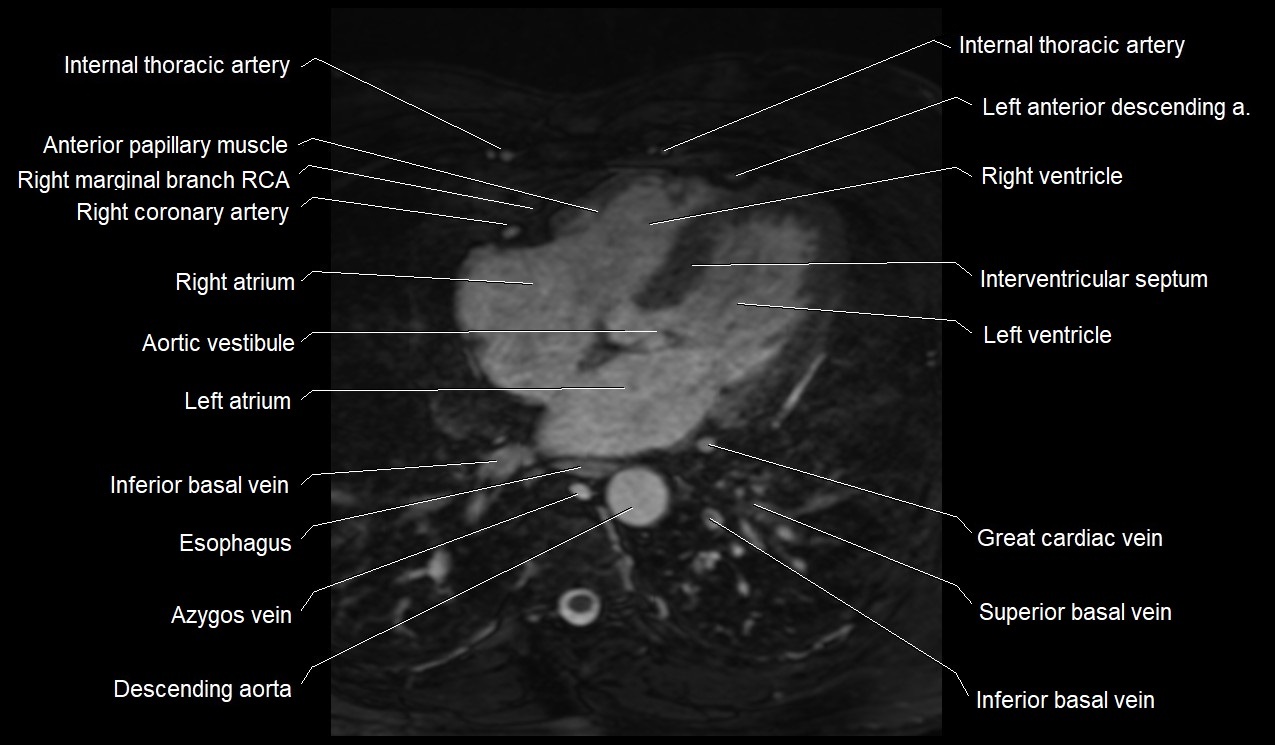

CT images